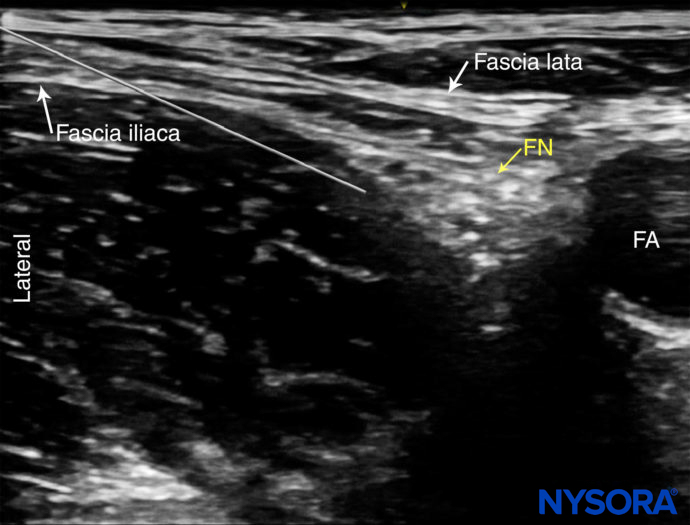

Orientation begins with the identification of the femoral artery at the level of the femoral crease. Commonly, the femoral artery and the deep artery of the thigh are both seen. In this case, the transducer should be moved proximally until only the femoral artery is seen (Figure 1a, b). The femoral nerve is lateral to the vessel and covered by the fascia iliaca; it is typically hyperechoic and roughly triangular or oval in shape (Figure 2a, b). The nerve is enveloped within two layers of the fascia iliaca. The femoral nerve typically is visualized at a depth of 2–4 cm.

FIGURE 2. (A) Cross-sectional anatomy of the femoral nerve (FN) at the level of the femoral crease. The FN is seen on the surface of the iliopsoas muscle covered by fascia iliaca (white arrows). The femoral artery (FA) and femoral vein (FV) are seen enveloped within their own vascular fascial sheath created by one of the layers of fascia lata. (B) Sonoanatomy of the FN at the femoral triangle.